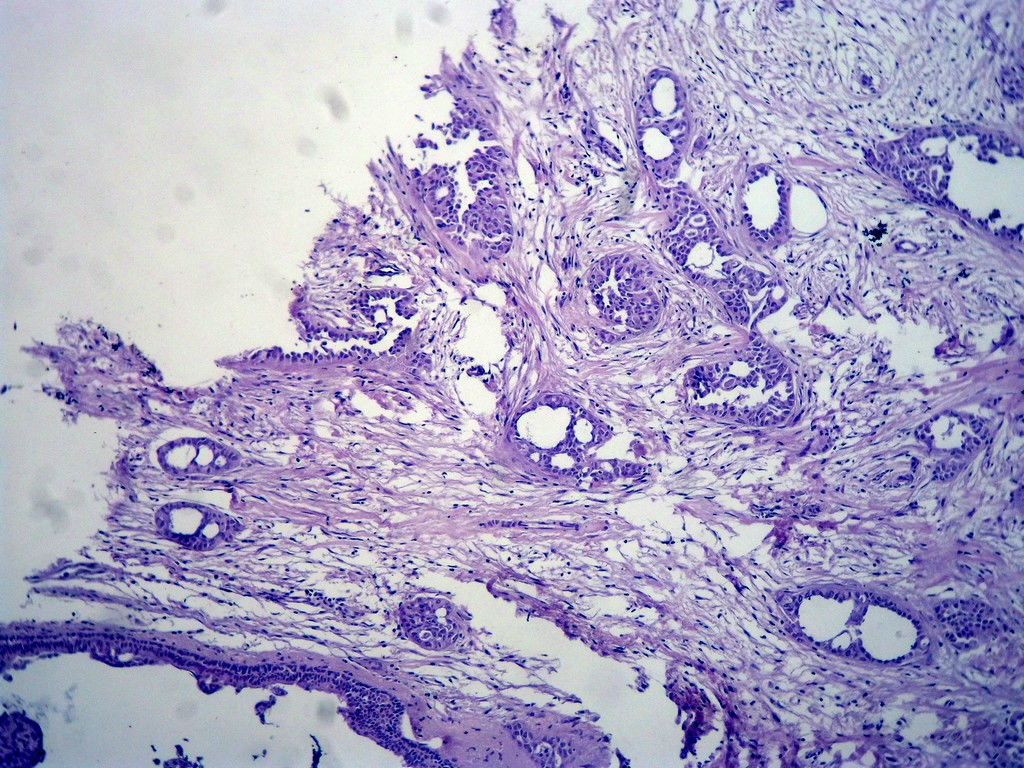

今天的一例术中冰冻。女,49岁,乳腺肿块。人气不旺,换个标题

腺病?癌?其他?(12楼常规,24楼免疫组化及会诊结果)图1

标签:浸润性导管癌 分泌癌 硬化性腺病

乳腺分泌型癌

占楼传常规1-11为冰对。

浸润性导管癌。冰冻切片的诊断是很困难,直接诊断癌风险很大,但是在明显正常的导管间这种成片、成巢有腔的细胞团块也不是良性的表现,有的还似乎有围绕正常导管生长的倾向。诊断ADH还可以,但是不能归到任何一种DCIS的生长方式里。这例值得我好好学习。